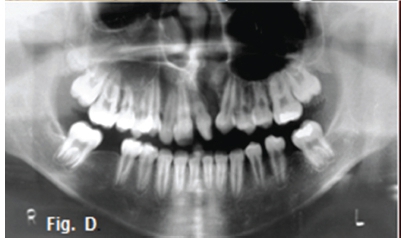

The above images are examples of cleft palate and cleft lip. After clubfoot, cleft lip and cleft palate are the most frequently encountered congenital deformities. Cleft palate is a defect in the continuity of the palate resulting from incomplete development or maturation of embryonal processes. It is often but not invariably accompanied by cleft lip. Cleft palate may be an isolated occurrence or may be part of various specific syndromes. Cleft palate varies greatly in severity and tissue involvement. The hard or soft palate, or a combination of both, can be affected. Frequently, clefts of the hard palate extend anteriorly through the alveolar ridge and lip, deviating to the right and/or left in the premaxilla. Sometimes, although much less often, the premaxillary defect is bilateral (Figs. A, B, C). When the alveolar ridge is affected, teeth in the region may be missing (Fig. D), deformed, or displaced, or supernumerary teeth can be present. The etiology is not completely understood, but heredity plays a role. Chromosomal abnormalities and exogenous factors are recognized as having etiologic impact, and a positive relationship between advancing age of parents and frequency of cleft has been demonstrated On occasion only the soft palate or a bifid uvula is involved (Fig. E). In unilateral cases of combined total cleft lip and palate, the vomer is in most cases connected with the palatal plate of the non-affected side In about half of cases, other developmental abnormalities are present. These include a variety of specific syndromes, congenital heart defects, polydactyly or syndactyly, hydrocephalus, spina bifida, and mental deficiency.